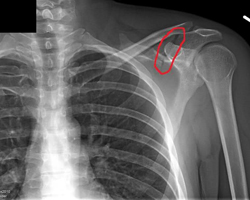

Broken shoulder

The clavicle (collarbone) fracture is one of the most commonly seen broken bones, fracture of the humeral head (the ball) is quite common an older person who falls.

Depending upon the amount of comminution (into how many pieces the humeral head breaks) surgery may or may not be required. Initial treatment usually begins with a sling.

The scapula or shoulder blade is a flat bone and very difficult to break. The mechanism is usually a direct blow. Any scapula fracture needs to be evaluated for related injuries.